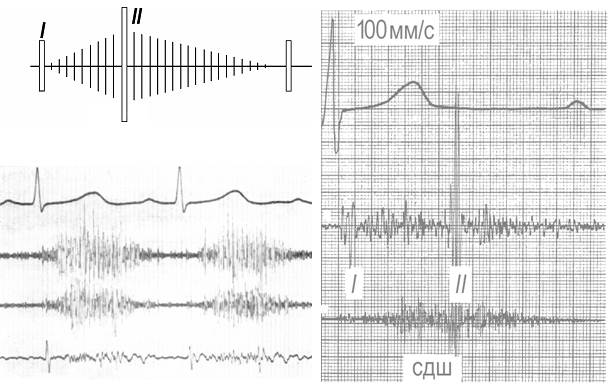

Рис. 8. Шум незаращения артериального протока. Слева вверху - схематическое изображение звуковой картины, внизу - данные ЭКГ и ФКГ (систолодиастолический шум, II тон плохо дифференцируется). Справа - второй вариант звуковой картины на ФКГ: систолодиастолический шум (СДШ), резкое усиление II тона. Запись с точки 2 лс.